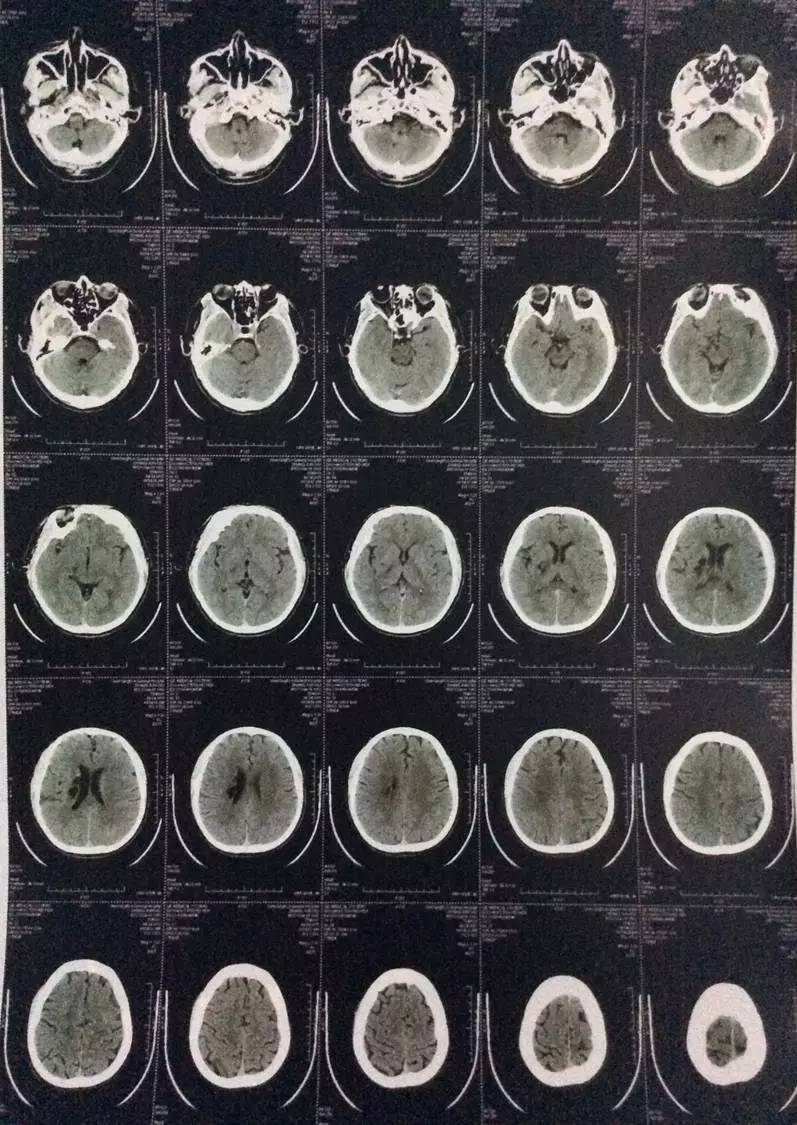

影像学检查:

右侧椎动脉颅内段局限性显示纤细,余脑血管未见明显异常。

脑干及右侧基底节见点片状低密度,部分病灶边界清晰,余脑内未见明显异常。